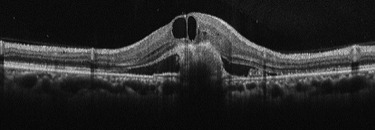

加齢黄斑変性

萎縮型は、加齢の影響で黄斑組織が委縮してしまいます。特徴としては、進行がとてもゆっくりで、急激な視力低下をもたらさないということが挙げられます。経過観察が重要になります。

滲出型は、新生血管というもろい血管が生えてきます。血管が破れて出血や、血液中の水分がもれて、黄斑部に浮腫が生じ、障害を起こします。日本人の加齢黄斑変性の患者様の多くはこの滲出型と言われています。症状の進行が早く、著しい視力低下がみられるので、早期診断・早期治療が重要になります。

治療としては、萎縮型の多くは特別な治療を必要とすることはなく、経過観察が重要となります。一方、滲出型は、新生血管を抑制する抗VEGD療法や光凝固術による治療を必要とすることがあります。当院では、必要に応じて連携する医療機関をご紹介しております。